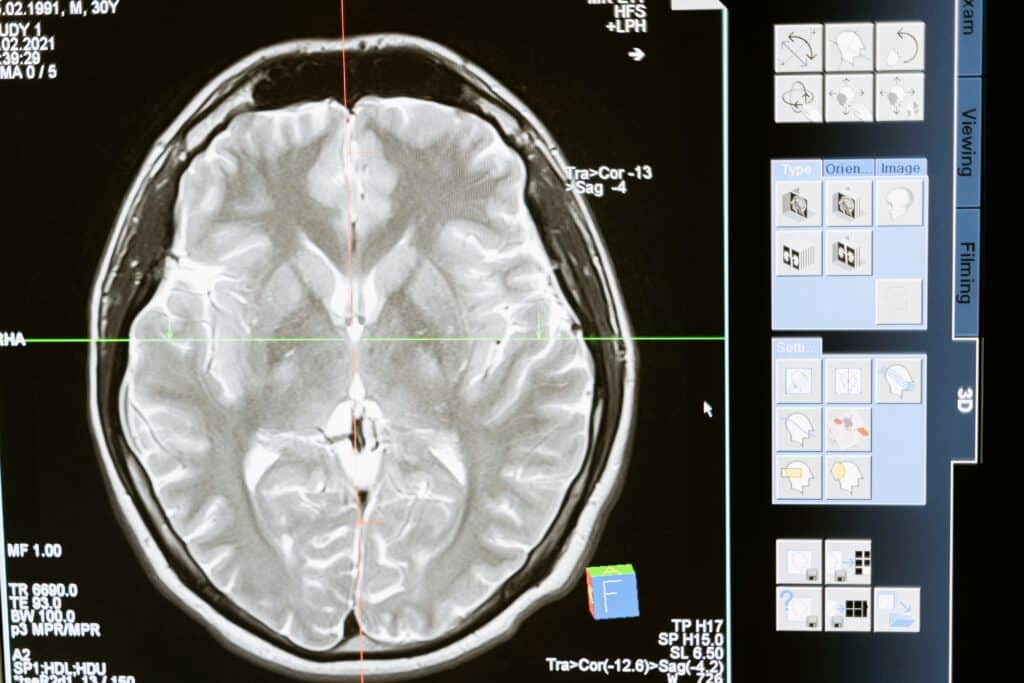

Il reste encore de nombreux mystères à éclaircir concernant le cerveau et son vieillissement. « L’imagerie par résonance magnétique fonctionnelle reflète l’augmentation de l’apport en sang dans les régions actives du cerveau, fournissant l’oxygène et les nutriments nécessaires aux neurones. La comparaison au fil du temps des signaux IRMf de personnes de groupes d’âge différents ou de ces mêmes personnes permet de gagner une meilleure compréhension de l’architecture et du fonctionnement du cerveau humain. Cette démarche a mis en lumière les changements normaux et pathologiques liés à l’âge à l’oeuvre dans le cerveau ainsi que les différences entre individus, contribuant ainsi à la détection et à la caractérisation des troubles neurodégénératifs, tels que la maladie d’Alzheimer », explique un communiqué du CORDIS, l’organisme en charge des projets financés par l’UE.

« Certaines caractéristiques fréquentes détectées par IRMf, notamment la désactivation de certaines régions du cerveau pendant le contrôle cognitif et l’activation accrue des zones préfrontales au cours du vieillissement, ont toutefois donné lieu à des questions d’interprétation », explique Anna Rieckmann, la coordinatrice du projet SIMULTAN.

Financé par le Conseil européen de la recherche, ce projet a pour vocation d’analyser les signaux liés au vieillissement. « Lorsque les neurones sont actifs, ils ont besoin d’une plus grande quantité d’oxygène et de nutriments (demande métabolique), ce qui entraîne la dilatation des vaisseaux sanguins de cette région et, partant, augmente le débit sanguin et l’apport en oxygène (contributions hémodynamiques). Cette réaction génère un surplus d’hémoglobine oxygénée dans la région concernée, visible par imagerie IRMf. L’ennui, c’est que les nombreux processus qui associent l’activation des neurones à l’augmentation des signaux IRMf sont complexes et ne sont pas pleinement compris », ajoute le CORDIS.

« Par exemple : Les différences entre les signaux IRMf des adultes âgés et ceux des adultes plus jeunes reflètent-elles des différences en termes d’activité neuronale ou de débit sanguin et d’apport en oxygène des systèmes vasculaires plus âgés ?», s’interroge Anna Rieckmann.